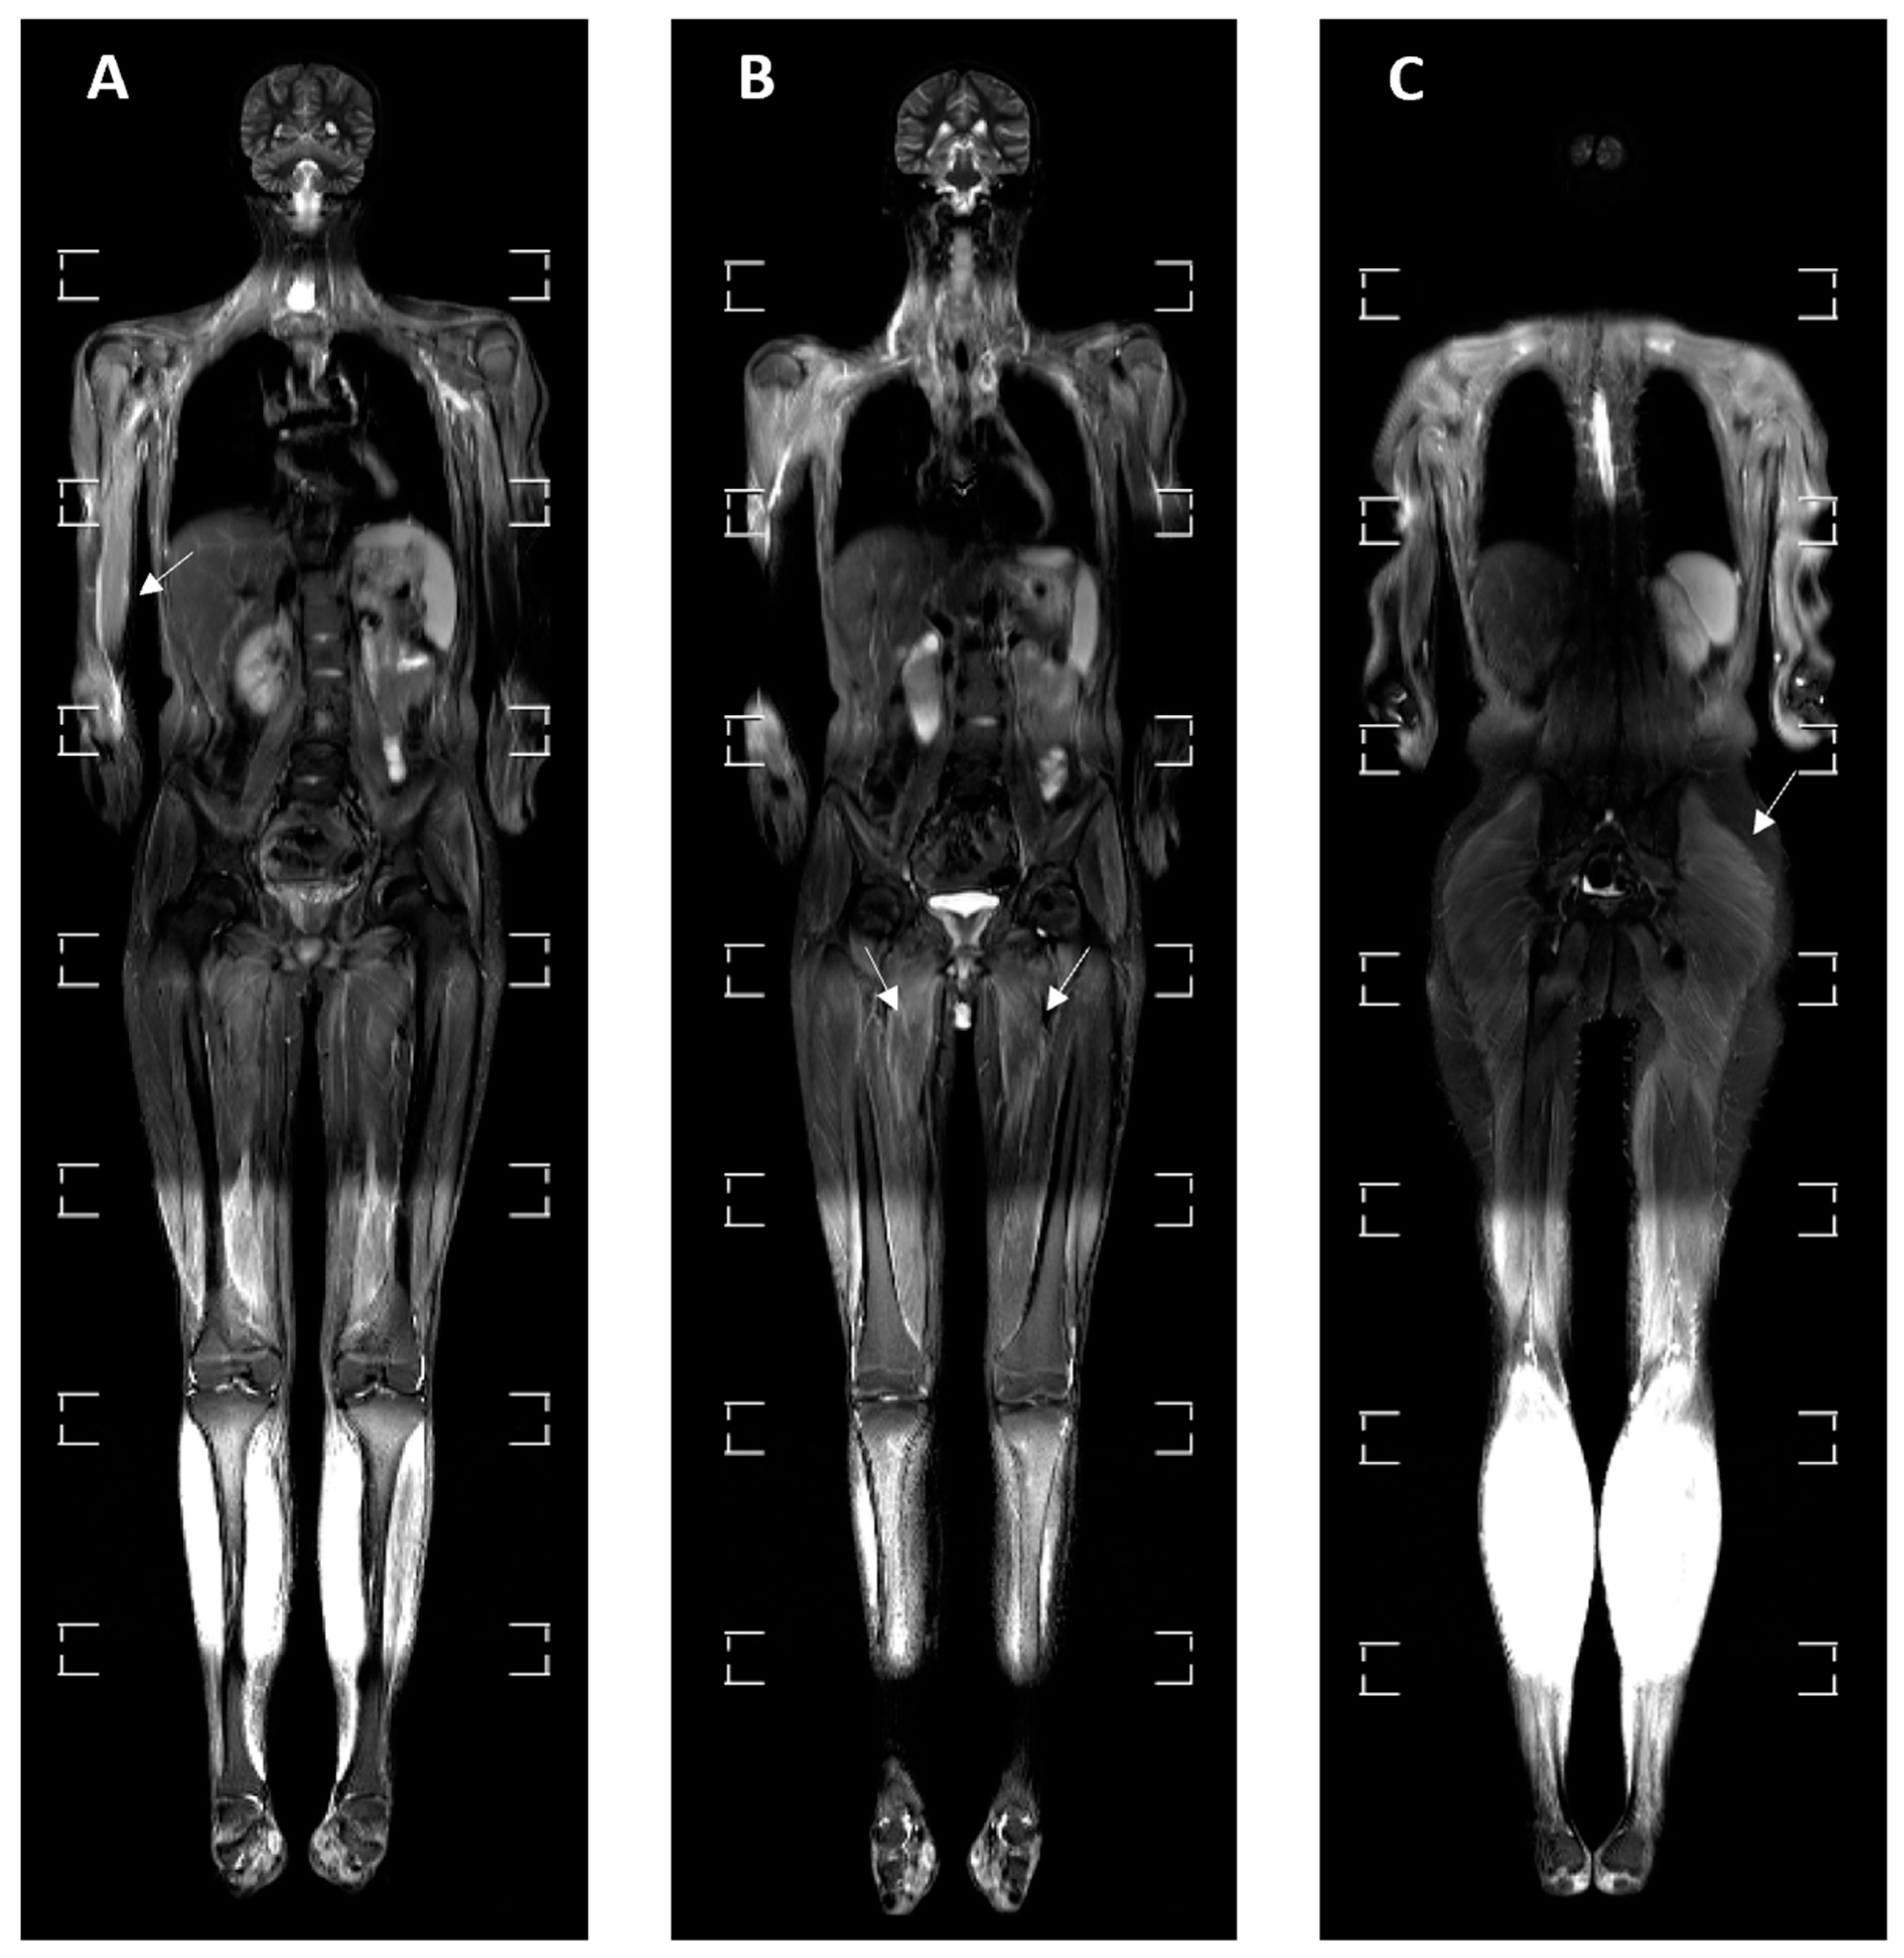

3.4. MRI Findings

| BME | 8 (24.24%) | 2 (22.22%) | 0 | 3 (42.86%) | 3 (30%) | p = 0.288 |

| Myositis | 10 (30.30%) | 1 (11.11%) | 6 (85.71%) | 1 (14.29%) | 2 (20%) | p = 0.004 * |

| Liver enlargement | 1 (3.03%) | 0 | 0 | 1 (14.29%) | 0 | p = 0.280 |

| Spleen enlargement | 3 (9.09%) | 0 | 0 | 1 (14.29%) | 2 (20%) | p = 0.352 |